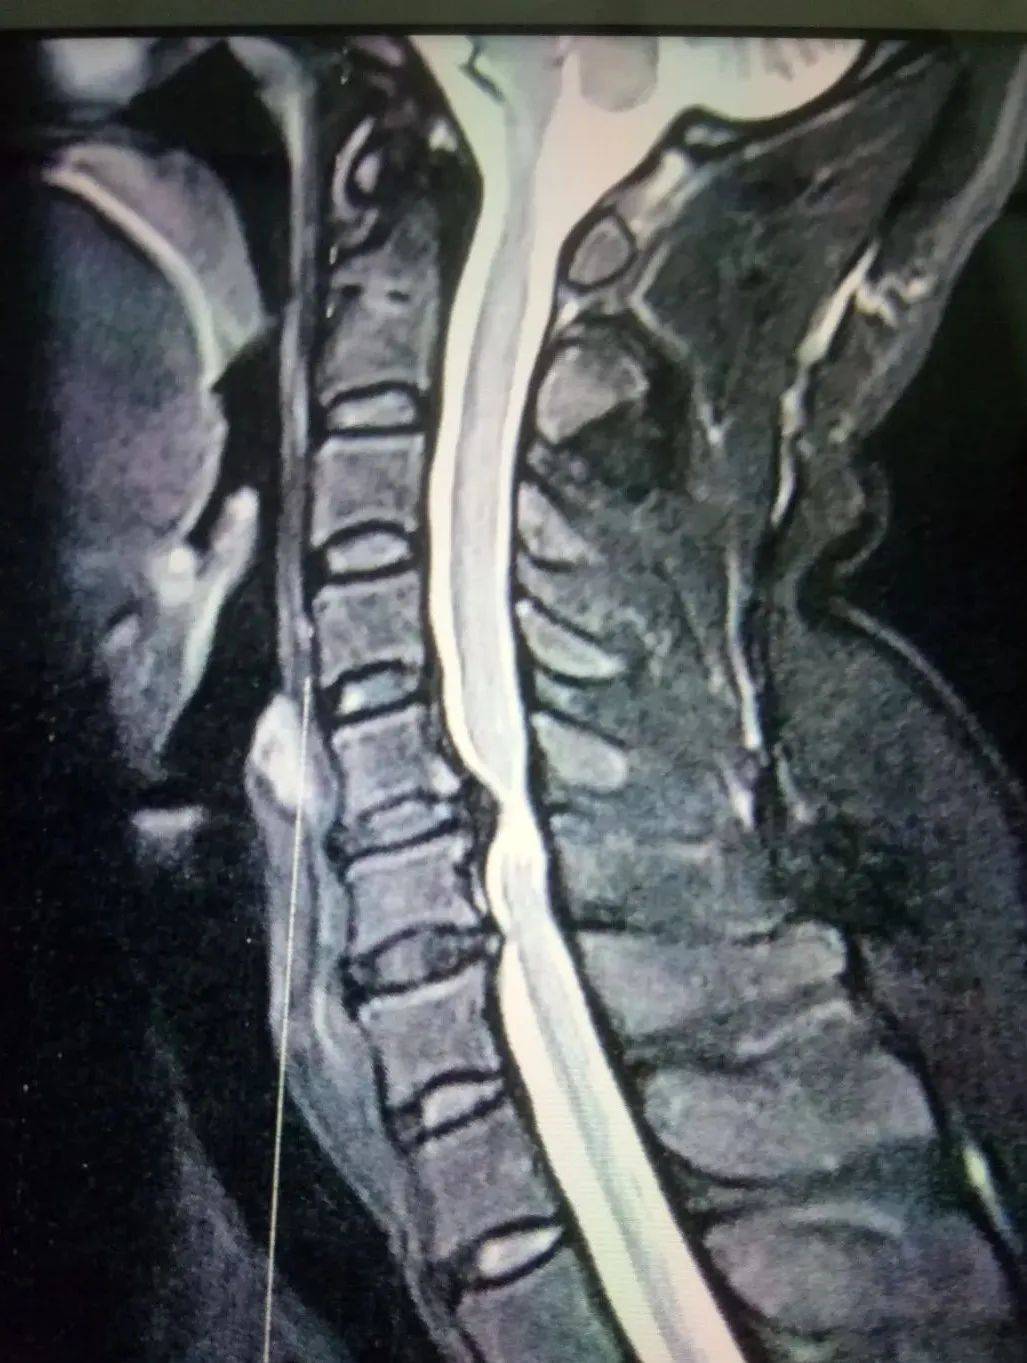

杨✘,女,52岁,2022年8月8日有家人搀扶初诊,自述 : 一年前自感头晕,上肢抬肩和下肢走路无力,家人很快送至市医院,初步诊断为(脑梗塞),住院输液等药物治疗五十余天,上肢和下肢障碍没有多大改善;又经多方会诊拍颈椎核磁共振片子所示 :

颈椎核磁共振所见 : 颈椎间盘突出,压迫脊髓严重,医院建议做手术;因家人和她本人惧怕手术,经朋友介绍来到我门诊埋线治疗。